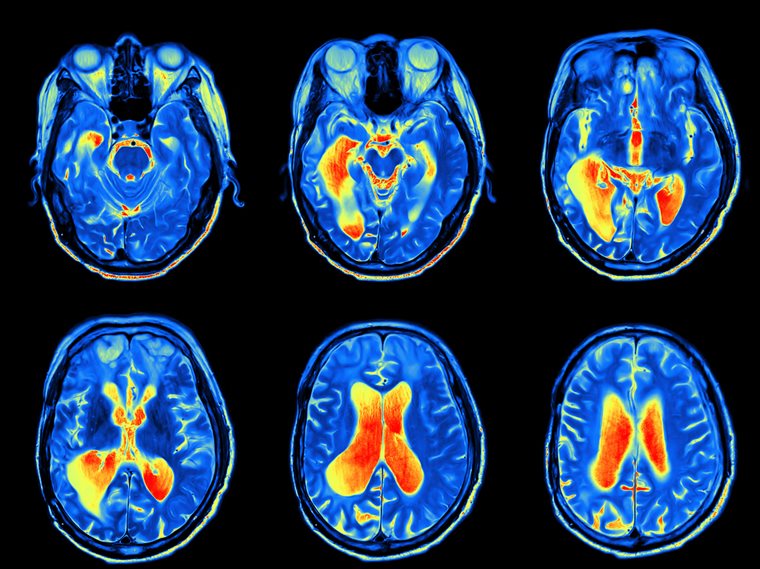

Nuclear Medicine and PET are the heart of modern precision medicine

Nuclear medicine and PET are at the heart of modern precision medicine—guiding oncology, cardiology, neurology, and theranostics with unparalleled molecular insight. Working in this field is not just about competence; it’s about innovation, leadership, and improving patient outcomes in a rapidly evolving specialty.